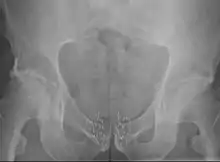

La curiethérapie pour traiter le cancer de la prostate peut être appliquée soit par l'implantation permanente de grains BDD soit par curiethérapie HDD temporaire[19],[59],[60]. L'implantation permanente des grains est adaptée aux patients qui ont une tumeur localisée et de bon pronostics de guérison[8],[59],[61],[62]. Il a été démontré que c'est un traitement très efficace contre la récidive[6],[8]. La taux de survie est similaire à celui observé avec la radiothérapie externe ou la chirurgie (prostatectomie radicale), mais avec moins d'effets secondaires tels que l'impuissance et l'incontinence[14]. La procédure peut être réalisée rapidement. Les patients sont généralement en mesure de rentrer chez eux le jour même du traitement et de retourner à leurs activités normales après 1 à 2 jours[3]. L'implantation permanente de grains est souvent une option moins invasive du traitement par rapport à l'ablation chirurgicale de la prostate[3].

La curiethérapie temporaire HDD est une approche nouvelle pour traiter le cancer de la prostate, mais reste moins fréquemment utilisée, moins fréquente que l'implantation permanente de grains. Cette technique (également appelée boost thérapie) est employée de manière à offrir une dose supplémentaire par rapport à la radiothérapie externe. En effet, elle offre une méthode alternative pour délivrer une dose élevée de radiothérapie adaptée au type de tumeur de la prostate, tout en épargnant les tissus environnants de l'exposition aux rayonnements[9],[10],[60],[61],[11],[63]. La curiethérapie HDD comme amélioration pour le traitement du cancer de la prostate signifie aussi que les séances de radiothérapie externe peuvent être plus courtes que quand la radiothérapie externe est utilisé seule[9],[10],[63],[64].